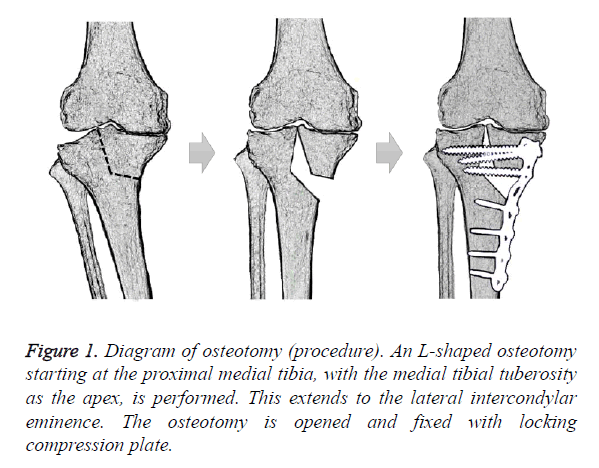

ゼロからはじめる! Knee Osteotomyアップデート | 日本 Knee。A. Stage 2 lateral knee osteoarthritis with HKA of 193。Functional and Radiographic Results of Arthroscopy-Assisted。膝の骨切り術に関する最新情報を提供する専門書。Functional and Radiographic Results of Arthroscopy-Assisted。裁断済みです。。定価12000